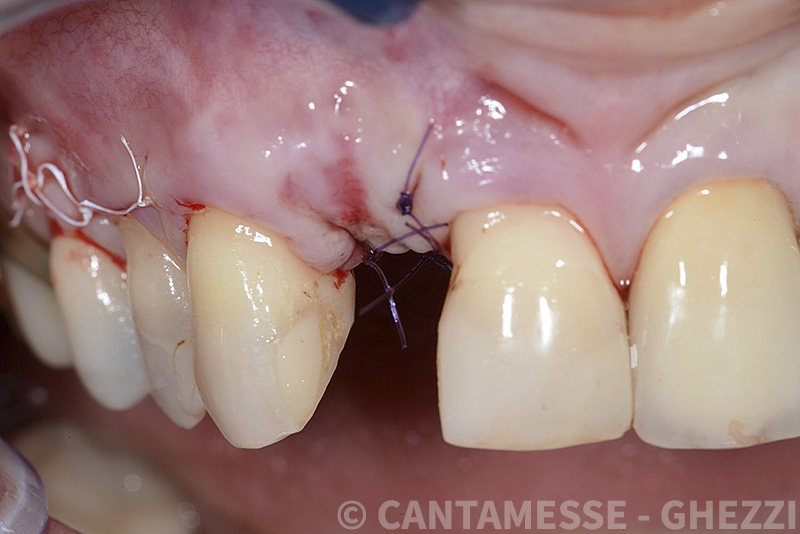

PREMESSA: in seguito all’estrazione dell’incisivo laterale superiore di destra, resasi necessaria per cause batteriche, si decide di affrontare il caso con il posizionamento di un impianto in sostituzione dell’elemento mancante dopo guarigione del sito infetto. Con tecniche rigenerative sia dei tessuti ossei mancanti a causa dell’infezione pregressa, sia dei tessuti gengivali che appaiono inizialmente troppo spostati in alto, si ripristina una corretta morfologia delle parabole (contorni) gengivali e delle papille interdentali (triangoli di gengiva tra due denti vicini).

Vengono utilizzati 2 tipi di provvisori: il primo, cementato ai denti vicini, viene utilizzato dal momento dell’estrazione del dente fino ad impianto osteointegrato (circa 6 mesi); il secondo, avvitato direttamente all’impianto, ha una funzione di prova estetica ma soprattutto di guida per la maturazione dei tessuti gengivali peri-implantari portandoli verso la maturazione completa prima di posizionare la corona finale in disilicato di litio.